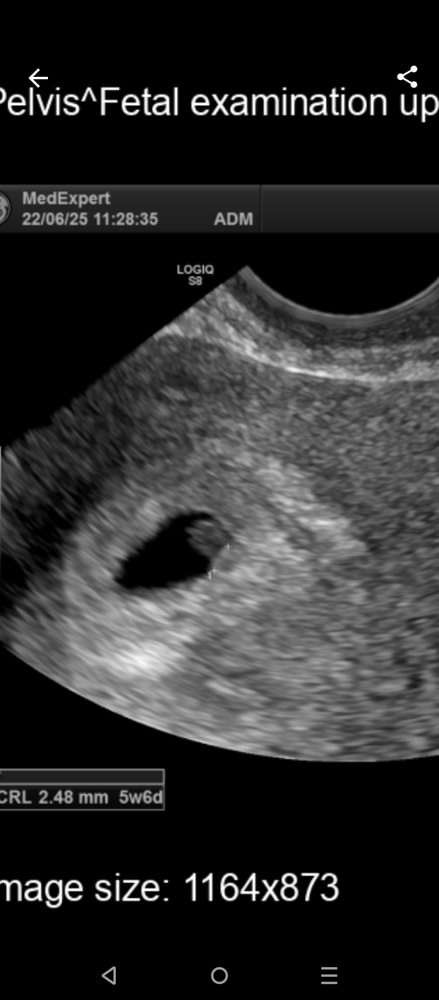

и еще узи… сегодня, от 30.06:

Эндометрий: гравидарный 15мм;

Полость матки:

плодное яйцо свд-15мм,

эмбрион 2,5 мм контуры нечетко , длина 2,5 мм , с/б +

ЖМ - 2,5 мм

врач молча намекнула на то что плод замирает…. Тип эмбрион нечеткий…

либо сказала срок маленький

фото прикрепляю